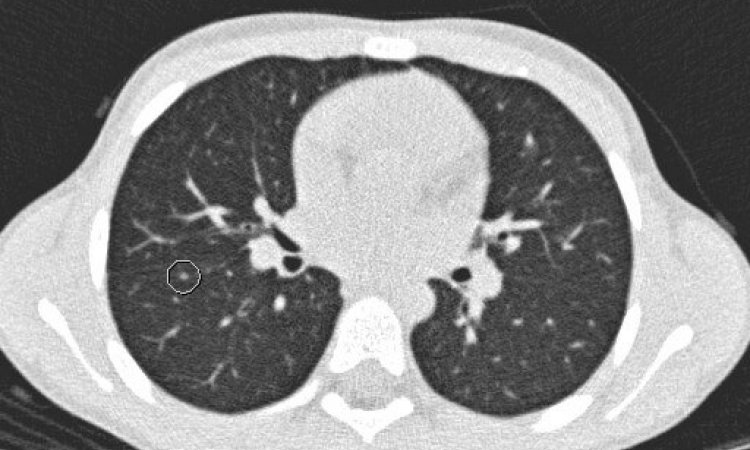

‘This is very early work from my current research that I want to share with the audience as a kind of future for MRI,’ she added. ‘This research is focused on establishing the benchmarks, to establish a proof of principle. Once we can say that there is an underlying genomic basis for an imaging phenotype then, in the future perhaps, we will be able to use imaging to guide treatment decisions and avoid multiple biopsies,’ she predicted. ‘We can’t biopsy 10 times, so that a patient becomes a pincushion. There is a limit. What we are doing is validating MR imaging as a virtual biopsy tool.

Recent technological advances have brought complementary innovations in genomics that, when coupled with innovations in MRI imaging, allow the spatial quantification of tumour heterogeneity and the clonal composition of the genomics, as well as how they change during treatment. ‘Hopefully this will provide, in the future, the basis for improved treatment and outcomes,’ she said. ‘We want to have personalised cancer therapies, and this may be a fundamental driver for this personalised oncology.’

More than getting the right drug to the right patient at the right moment, Dr Sala said effective cancer therapy could also be a question of getting the drug to the right part of a tumour. ‘We know that tumours are different, that they are composed of different habitats, different clusters. Some of these clusters will drive the resistance to chemotherapy – and this is what actually kills the patient,’ she pointed out. ‘If we can know, by evaluating the different parts of the tumour, which one will drive resistance to the standard chemotherapy, we may be able to offer a new drug immediately to a patient.’